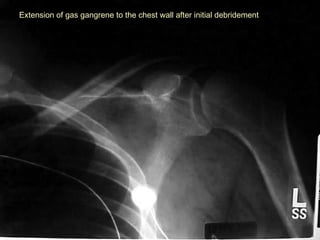

Extension of gas gangrene to the chest wall after initial debridementExtension of gas gangrene to the chest wall after initial debridement